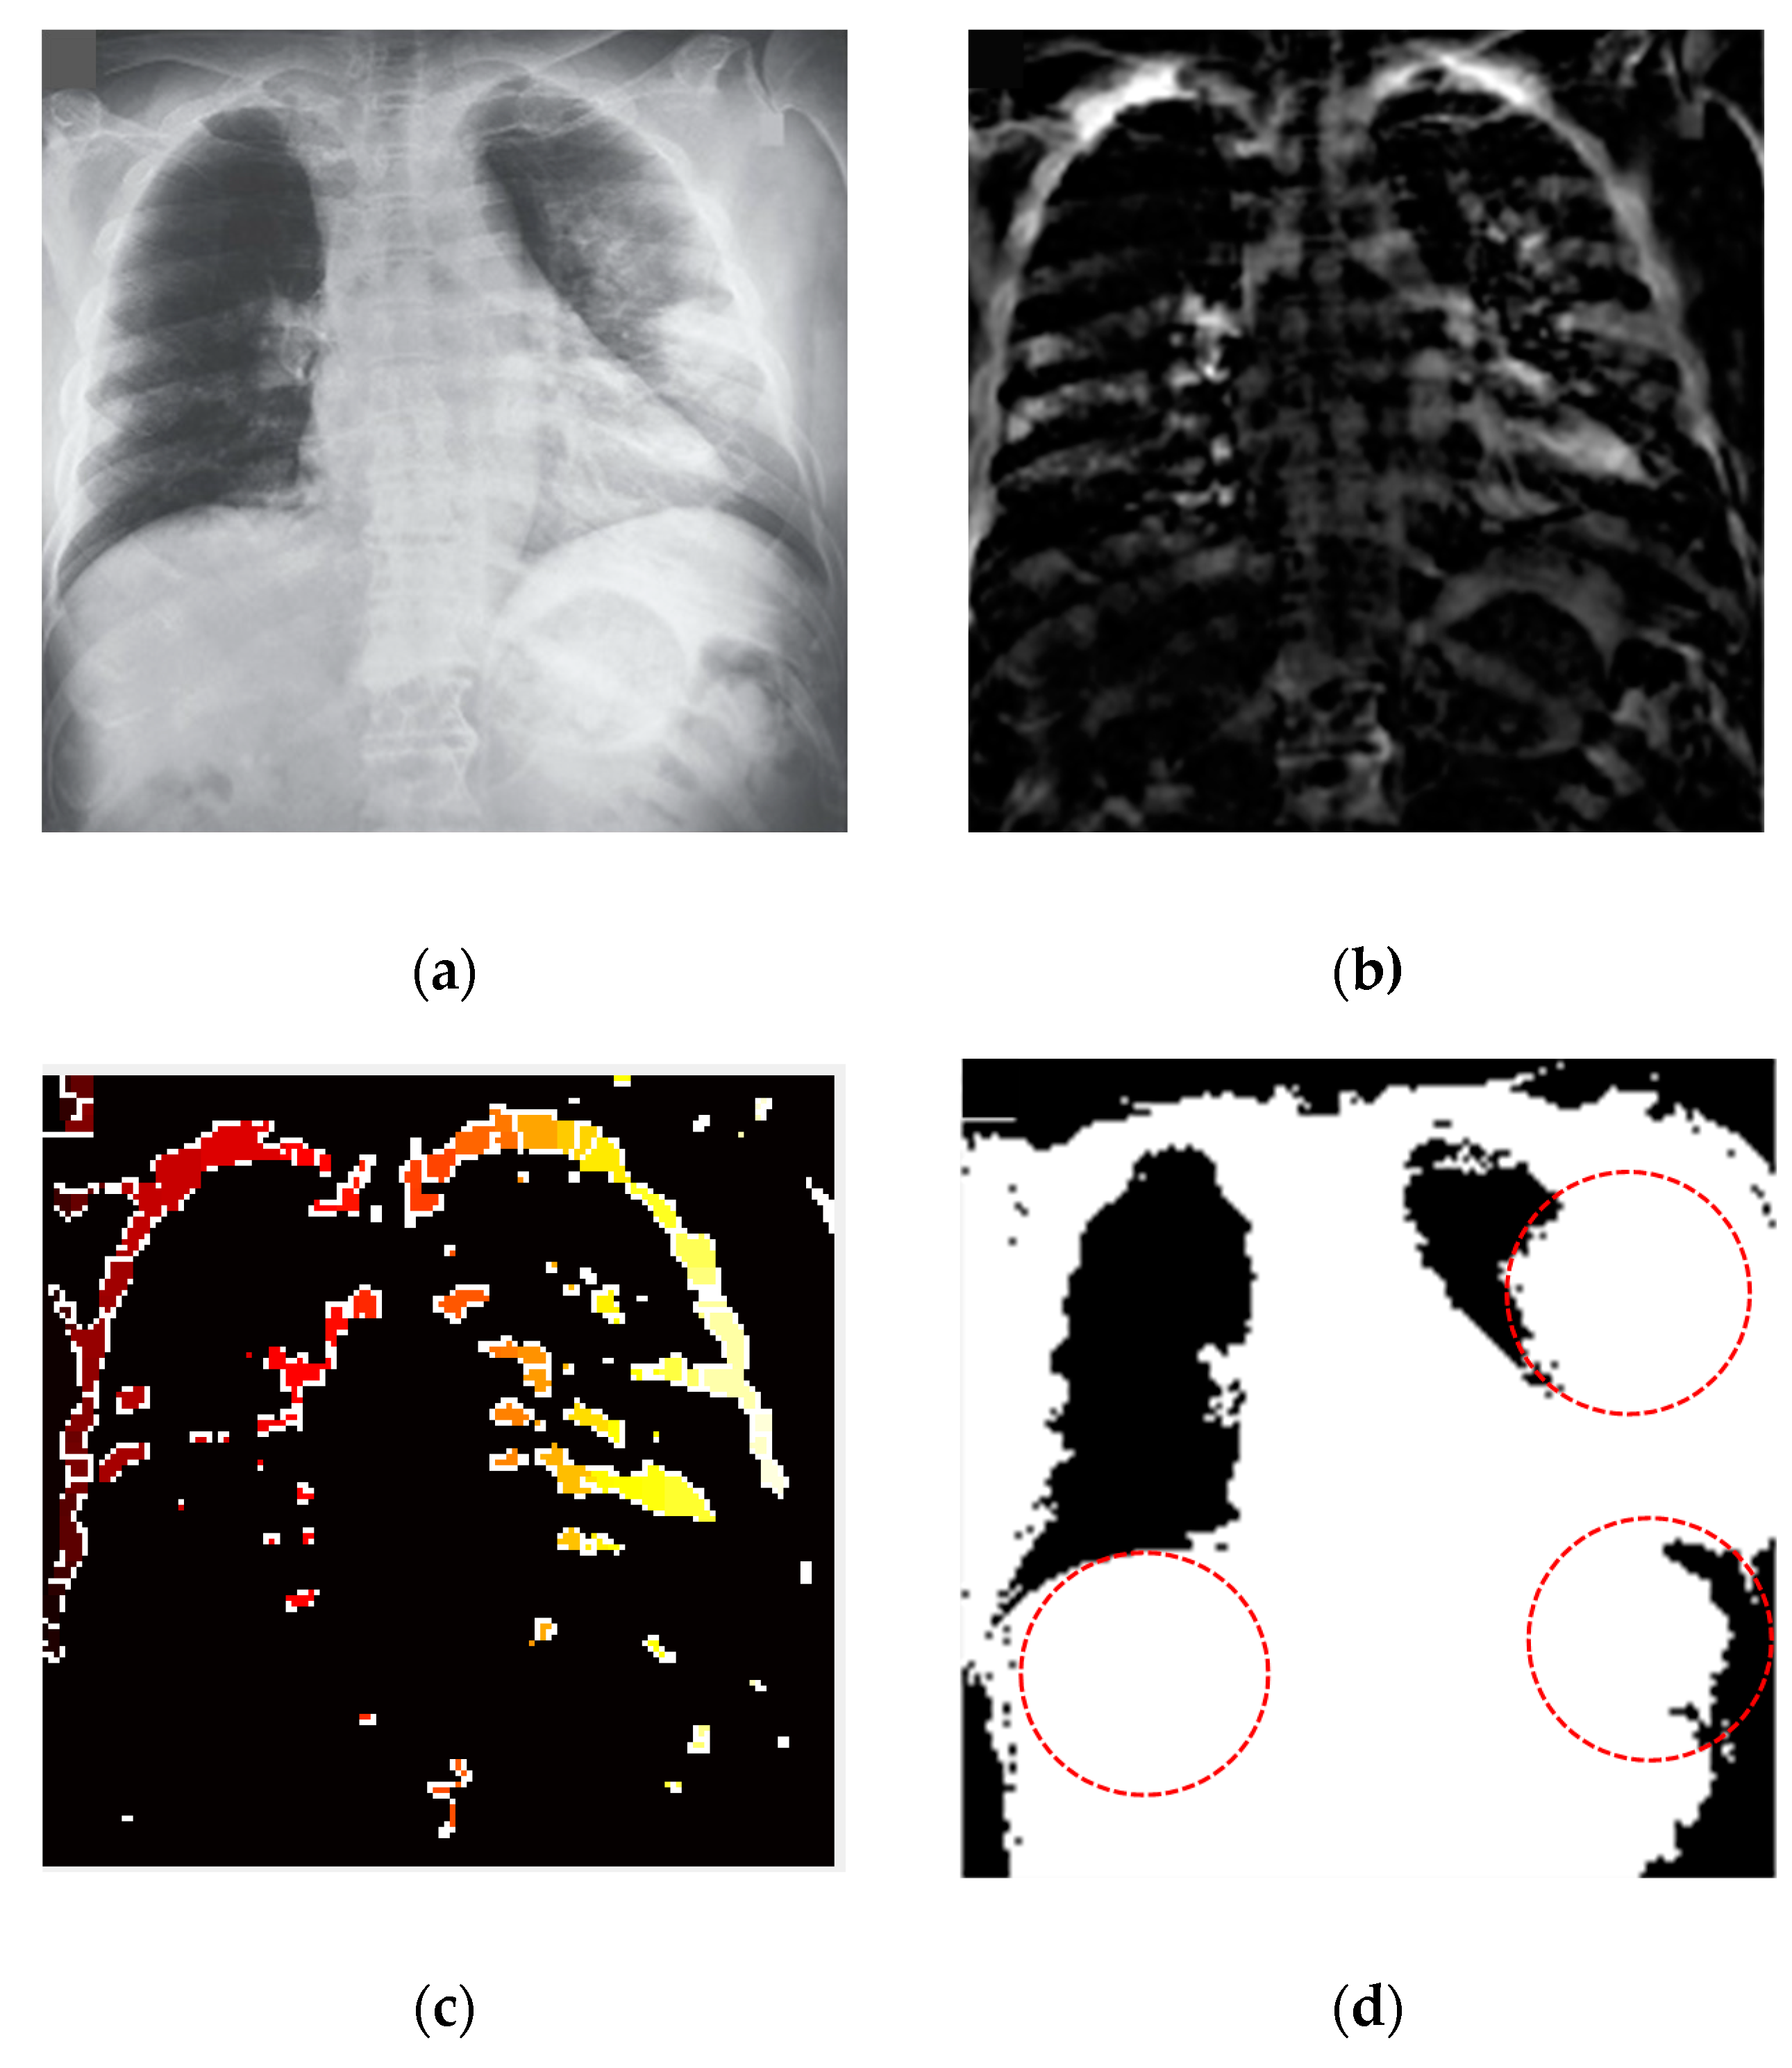

3.7. Segmentation of the COVID-19-Affected Region

For biomedical image segmentation, the watershed technique [55] provides better results compared to the other techniques, such as Fuzzy-C means (FCM). The conventional FCM algorithm suffers from some weaknesses in terms of initializing clusters center or determining an optimal number of clusters and sensitiveness to noise [56]. FCM segmentation method cannot detect the fracture regions from the X-ray images affected by the COVID-19. However, watershed segmentation is a fast, simple and intuitive method, which provides closed contours, requires low computational time and produces a complete division of the image in separated regions. Segmentation was applied for the non-trivial task of separating the fracture lung regions from the X-ray images. A watershed segmentation technique was applied to segment the fracture regions of each image owing to its relatively less computational complexity and capability of providing high accuracy in segmentation. This method separated touching objects in an X-ray image and provided a complete division. Figure 9 presents different stages of image processing from filtering to segmentation of significant regions from the COVID-19-affected lung X-ray images.

Figure 9.

COVID-19 segmentation by using the watershed technique (a) applied anisotropic diffusion for filtering (b) adjusting the filtered image (c) watershed RBG image (d) fracture lung region caused by the coronavirus (COVID-19).